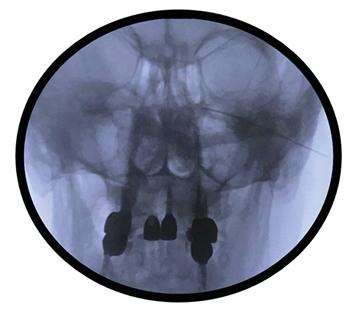

En revisión posterior en consulta, la paciente refirió persistencia de los síntomas asociando una importante incapacidad funcional para la vida diaria y afectación emocional. En vista de la eficacia transitoria de las técnicas realizadas hasta la fecha, la persistencia de restos de tumor en la imagen control y de un examen físico en el que se evidenció gran afectación clínica de la paciente (anestesia para dolor y tacto en territorio de V1 y V2, reflejo corneal ipsilateral abólido, hipoacusia persistente, paresia facial izquierda, hipoestesia para dolor leve en hemicuerpo izquierdo y dolor selectivo sobre cicatriz), se propuso realizar radiofrecuencia pulsada del ganglio esfenopalatino izquierdo mediante abordaje infracigomático (Figura 2). Esta técnica se realizó sin incidencias, obteniéndose un alivio más duradero que la técnica transnasal, por lo que en el seguimiento de la paciente en consulta insistimos en avanzar con la radiofrecuencia térmica en una siguiente sesión.

Fig. 2. Fluoroscopia en proyección anteroposterior de abor-daje infracigomático del ganglio esfenopalatino.